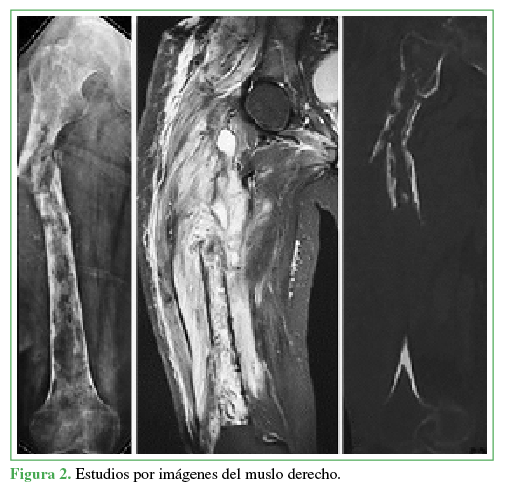

Se obtuvieron nuevas radiografías y se realizó una tomografía computarizada que mostró imágenes heterogéneas compatibles con pandiafisitis femoral y seudoartrosis en su tercio proximal. La resonancia magnética reveló imágenes hipointensas pandiafisarias en T1, de patrón moteado, con compromiso cortical generalizado, que respetaba cóndilos y la cabeza femoral; imágenes hiperintensas en T2 tanto de hueso como de partes blandas, acordes al proceso infeccioso agregado (Figura 2).

Figura 2

Estudios por imágenes del muslo derecho.